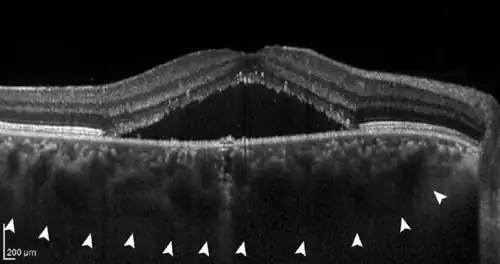

Central serous chorioretinopathy (pachychoroid stage II) with subretinal fluid (black triangle in the middle) and a markedly thickened, congested choroid (white arrowheads).

• If further damage to Bruch's membrane and the pigment epithelium causes fluid to accumulate under the retina, central serous chorioretinopathy (CSC) develops. In this stage, patients often have blurred vision and report a reduction in visual acuity with perception of a central "grey spot". In the majority of patients, spontaneous resolution of the subretinal fluid occurs within a few months, but recurs in up to 50% of cases. In some patients the fluid remains, making it a chronic disease; medical therapy or the application of various laser methods is possible.